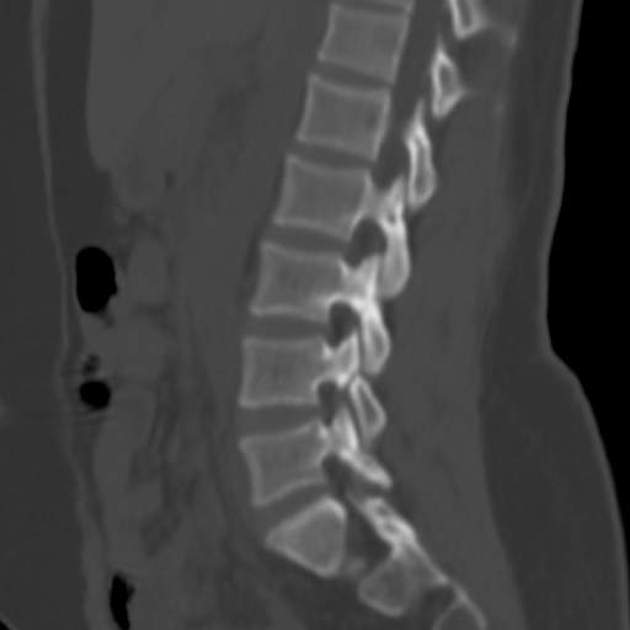

Компьютерная томография не является базовым исследованием для диагностики спондилолиза, потому что не определяет стадию патологического процесса, не визуализирует отёк костного мозга и не фиксирует активность воспаления в зоне перешейка. Спондилолиз представляет собой дефект межсуставной части дуги позвонка, связанный с нарушением костной непрерывности, часто протекающий с фазами нестабильности. Для диагностики назначаются магнитно-резонансная томография и рентгенография в функциональных проекциях. Оданко компьютерная томография при спондилолизе выявляет следующие анатомические признаки:

В нативном режиме определяется дефект перешейка межсуставной части дужки позвонка, чаще двусторонний, в зоне L5 или L4.

Фиксируется прерывистость контуров между верхним и нижним суставными отростками позвонка.

Определяется сглаживание, округление или склероз краёв дефекта при хроническом течении.

Визуализируются костные мостики, остеофиты или псевдоартроз в области лизиса.

В режиме высокоразрешающего сканирования костных структур выявляется минимальная щель, линии трещин или признаки незаращения костного перешейка.

- Форма, размеры и точное расположение дефекта фиксируются при аксиальной и сагиттальной реконструкции.

- Плотность костных краёв, наличие уплотнений и участков остеосклероза оцениваются количественно.

- Степень смещения тел позвонков при сопутствующем спондилолистезе уточняется в прямой проекции.

- Признаки хронического течения, включая костные адаптационные изменения, визуализируются при тонкосрезовом сканировании.

- Метод применяется для подтверждения диагноза при спорных результатах рентгенографии или при подготовке к оперативному лечению.